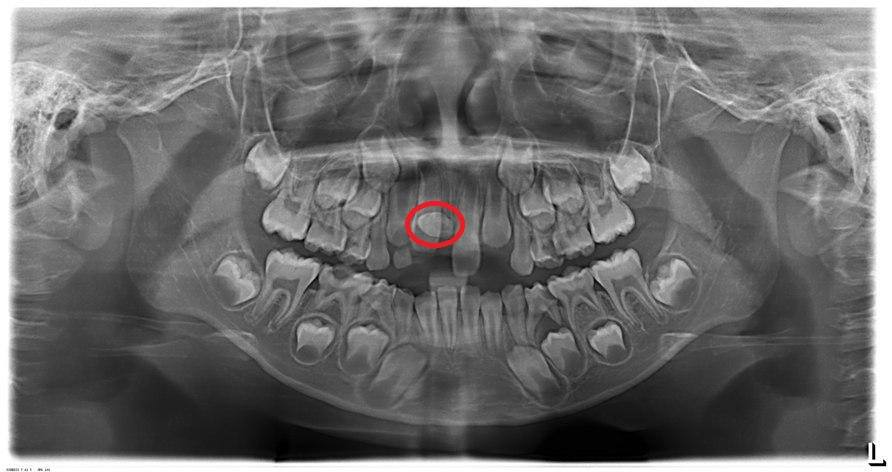

Thông thường, một hàm răng đầy đủ của con người có tổng cộng 32 chiếc răng và chỉ mọc 2 lần là răng sữa và răng vĩnh viễn. Tình trạng thiếu mầm răng vĩnh viễn là hiện tượng trên hàm răng có 1 hoặc nhiều răng không mọc lên (đa số là 1 – 2 răng).

Có mầm răng nhưng răng không mọc

Nếu có mầm răng nhưng không mọc được, đồng nghĩa với việc răng không thể trồi ra khỏi nướu và nằm lại trong xương hàm. Trường hợp này, các bác sĩ sẽ thực hiện thủ thuật nhằm bộc lộ răng ngầm trong xương. Sau đó, gắn khí cụ để kéo răng từ từ lên khỏi xương hàm để trở về đúng vị trí của nó. Nhờ vậy, người bệnh tránh phải sử dụng răng nhân tạo và hoàn thiện cấu trúc răng với đúng chức năng của nó.